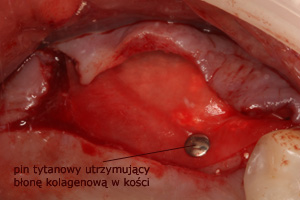

W każdej z metod, po odwarstwieniu błony Schneidera (błony śluzowej wyścielającej ściany zatoki), w wytworzoną przestrzeń wprowadzany jest materiał kościozastępczy będący zrębem dla powstawania nowej tkanki kostnej.